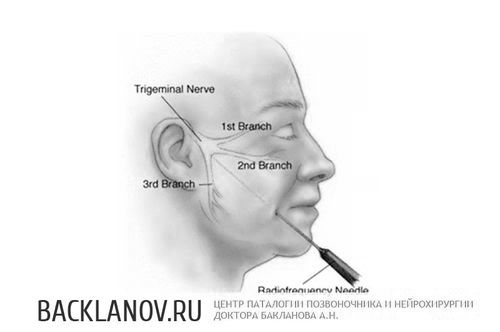

- Невралгії трійчастого нерва

- Радіочастотна абляція (Мірча)